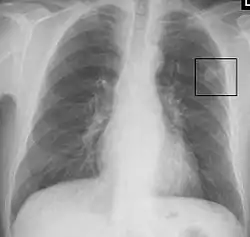

Kræft, cancer, (malign tumor eller malign neoplasi) er en gruppe af sygdomme, der involverer abnorm cellevækst, som potentielt kan gennemtrænge eller sprede sig til andre dele af kroppen.[1][2] Ikke alle tumorer kan betegnes som kræft; benigne tumorer spreder sig ikke til andre dele af kroppen.[2] Mulige tegn på kræft inkluderer en ny knude, unormal blødning, langvarig hoste, uforklarligt vægttab, ændringer i afføringen eller andet.[3] Disse symptomer kan indikere kræft, men de kan også have andre årsager.[3] Der er over 100 forskellige kendte kræftformer, der kan ramme mennesker.[2]

Kræft spreder sig ved at vokse i størrelse og ved udsæd (metastaser).

En ondartet svulst (malign tumor) opstår ved at cellerne er muterede og har mistet en række af deres normale egenskaber. Cellen kontrolleres ikke længere af de normale mekanismer. Cellen bliver mere udifferentieret, det vil sige at den mister sit formål og sin funktion, og væksten hæmmes ikke af de normale faktorer.

De almindelige mekanismer, der kan uskadeliggøre cellen er også uvirksomme, jvf immunsystemet og apoptose. Disse kaotiske celler kan så sprede sig direkte, via blodet eller lymfesystemet og skabe cellekolonier (metastaser) andre steder i kroppen.